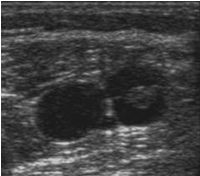

Ultraschall:

Thrombose im Querschnitt